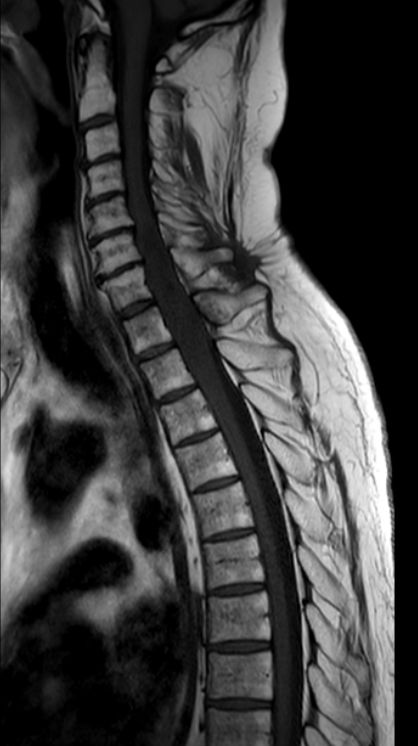

Myelon 63-jähriger Mann mit Querschnittssymptomatik. Auch nach Dekompression keine Motorik oder Sensorik der unteren Körperhälfte.

MRT T2W-Bild